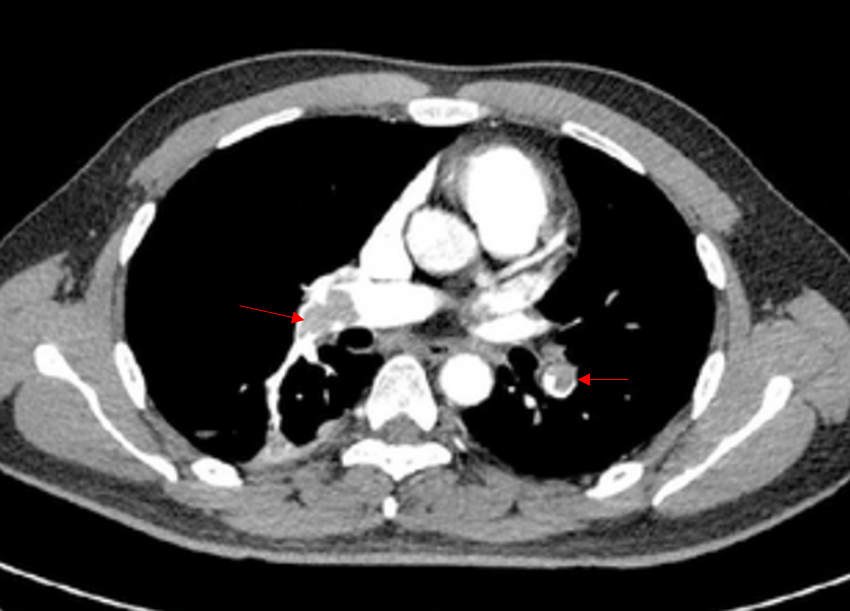

66세 여자가 하루 전부터 숨이 찬다며 응급실에 왔다. 1주 전에 외부병원에서 양쪽 인공무릎 관절치환술을 받고 누워 지냈다고 한다. 혈압 120/70mmHg, 맥박 84회/분, 호흡 20회/분, 체온 36.0℃이다. 가슴 청진에서 심음은 규칙적이고 심잡음은 들리지 않는다. 가슴 컴퓨터단층촬영 사진이다. 혈액 검사 결과는 다음과 같다. 치료는?

D-이량체 2,600 ng/mL (참고치, 220~740) 혈액요소질소/크레아티닌 10/0.9 mg/dL

Img | Chest CT: 양측 폐동맥 혈전 |

Imp: 폐색전증(pulmonary thromboembolism, PTE)

급성 호흡곤란, 장기간 bed rest의 과거력, CT상 혈전이 있으므로 PTE 진단 하, V/S stable하므로 rivaroxaban 등의 anticoagulation을 시행한다.

• CT에서 폐동맥 혈전이 보이므로 폐색전증으로 진단할 수 있다.